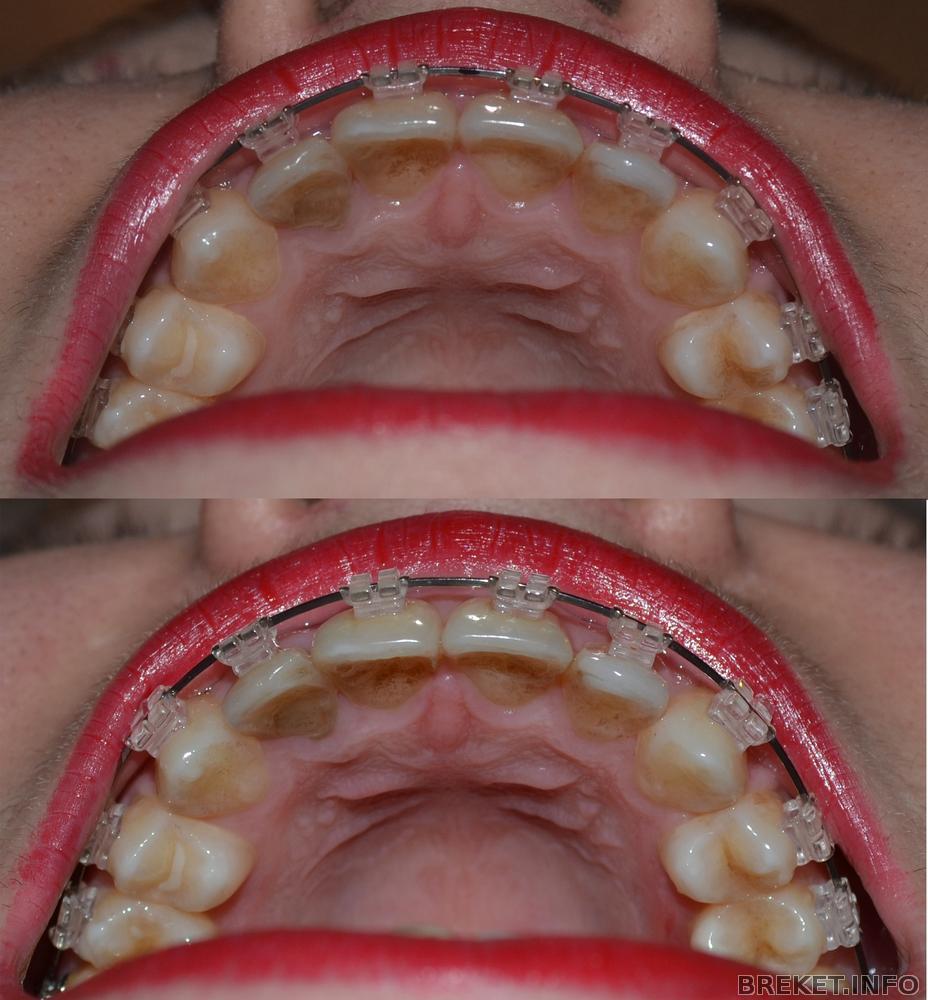

Сегодня ездила к орте. Спросила, когда же мы промежуток будем закрывать от удаленной единицы, она сказала, что промежутки закрываются на последних дугах. А потом подумала и сказала, ну ладно, чего мелочиться и поставила мне прямоугольную дугу на НЧ, накрутила чейн на 3 оставшихся резца и на них же повесила металлические лигатуры. Во как ![]()

Особо делиться нечем, прогресса уже нет, только появилась щель между клыком и четверкой на НЧ справа (на фото слева). Это упавший зуб приподнялся

Фотки все равно выкладываю для истории.